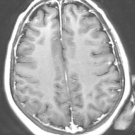

A 9-month-old boy with a history of developmental delay, failure to thrive, and intractable epilepsy of unknown etiology presented to the hospital with twitching of his right arm and face, concerning for...